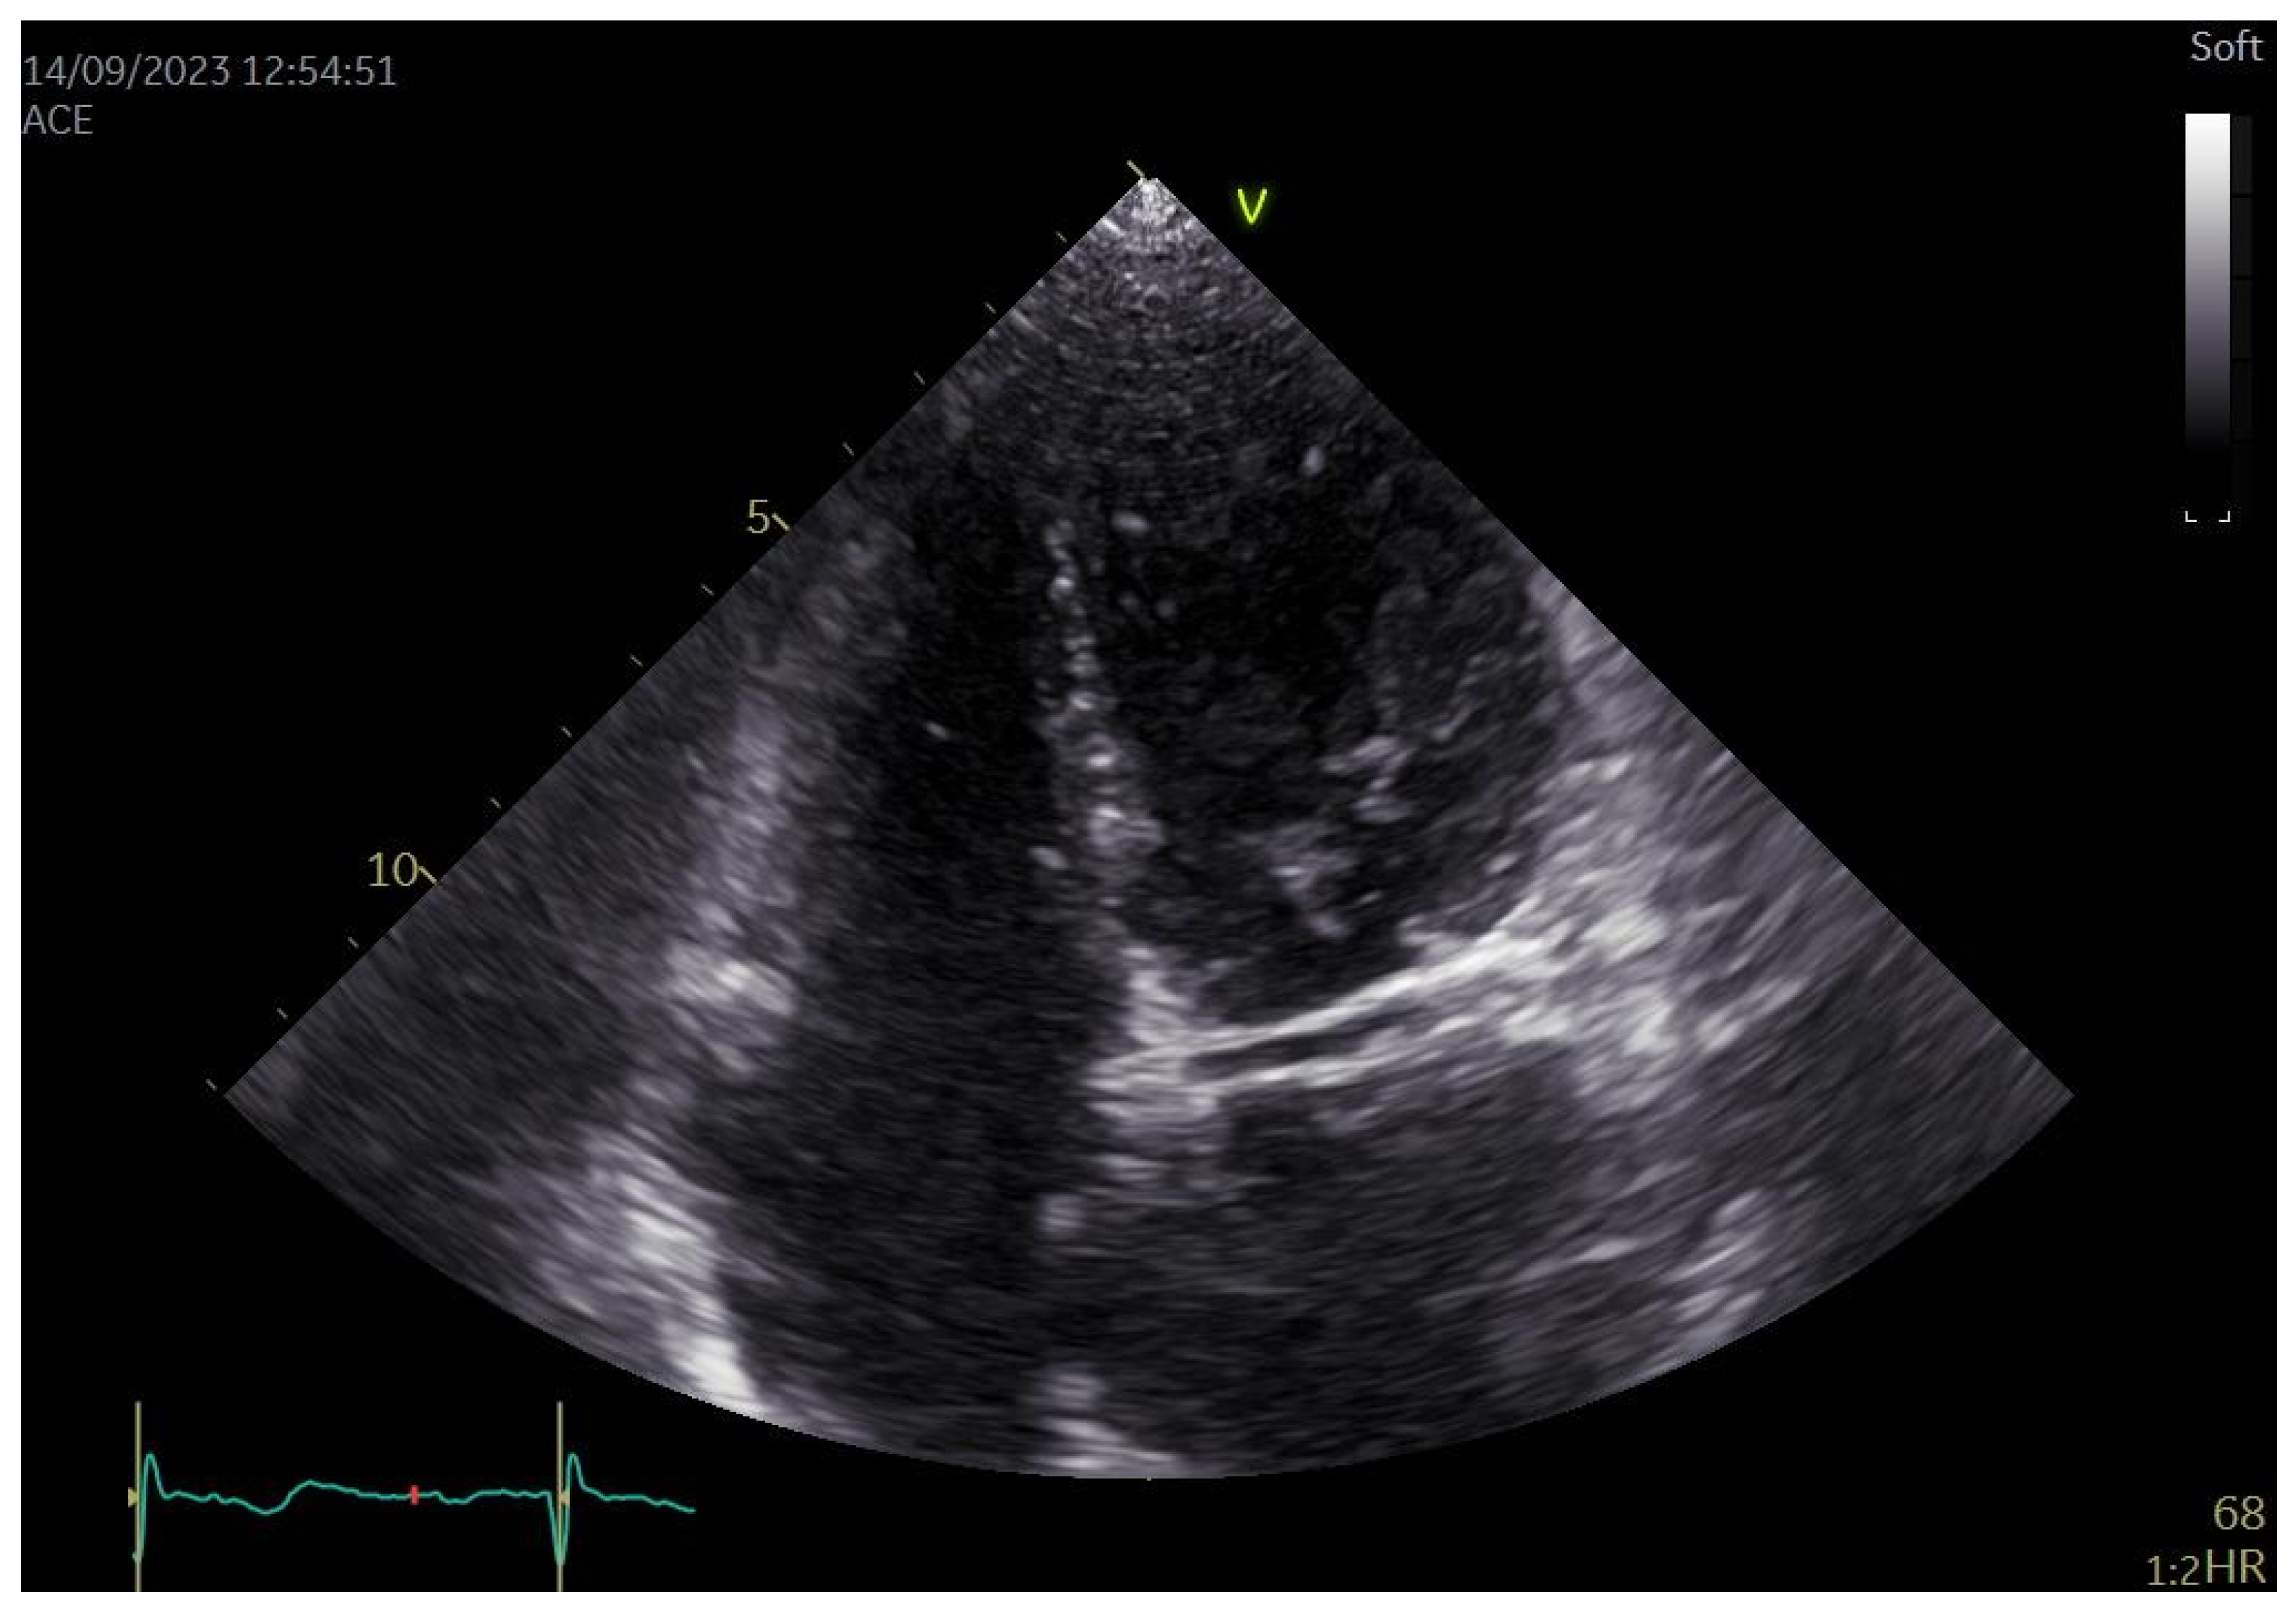

3.3. Echocardiographic

| Echocardiographic Feature | Number of Patients | % |

|---|---|---|

| Enlarged LA | 11 | 30 |

| MR | 14 | 38 |

| MS | 0 | 0 |

| AR | 3 | 8 |

| AS | 3 | 8 |

| TR | 8 | 22 |

| TS | 0 | 0 |